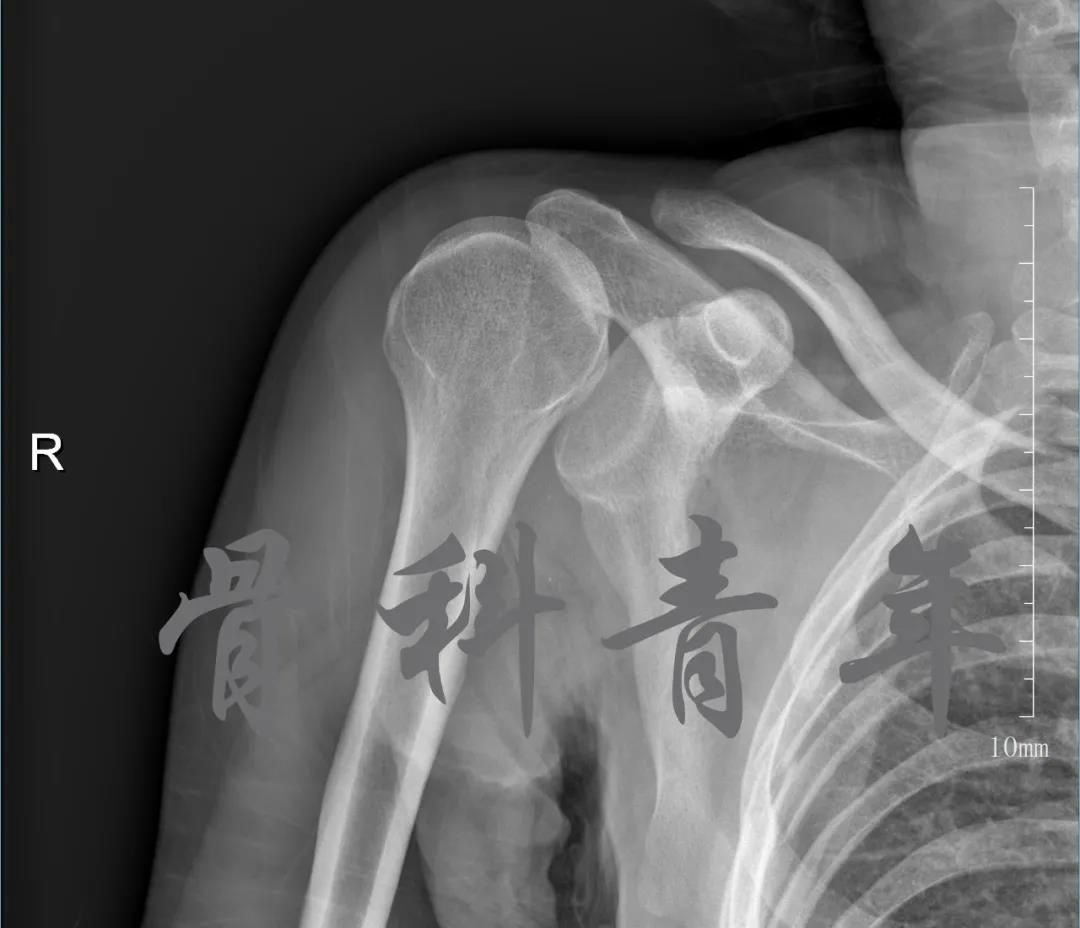

当地接诊医生应该说还是很负责的,同时拍了健侧片对比:

影像科报告,骨科医生光看报告行吗?

磁共振检查也完善了,还是报了个肩关节半脱位……影像科已经把坑挖好了……

接诊医生直接跳坑里了